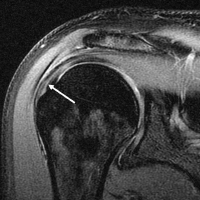

정상 어깨의 MRI 촬영 이미지(왼쪽)와 회전근개파열 어깨의 MRI 촬영 이미지(오른쪽)